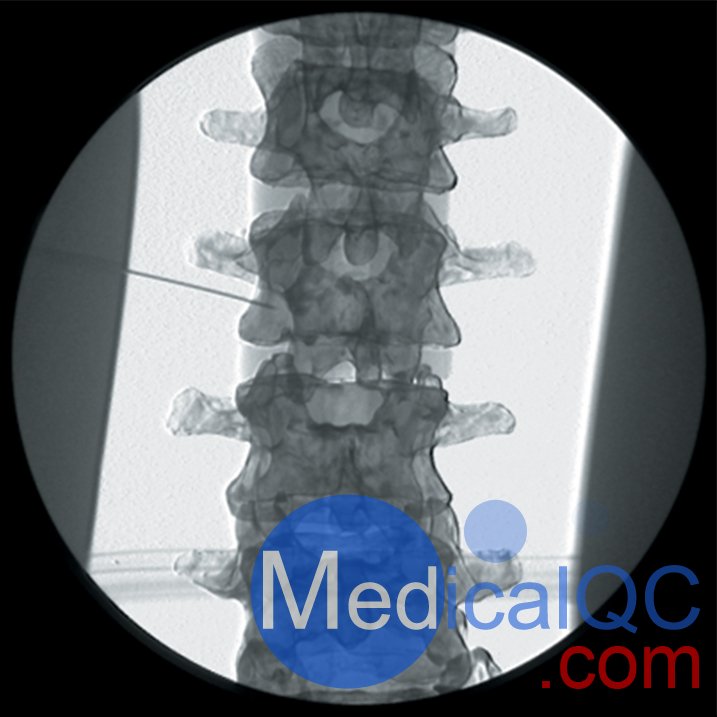

AR351脊椎穿刺模體,Adam,Rouilly脊椎穿刺模體是區(qū)域麻醉模擬人體模型,由曼徹斯特和索爾福德疼痛中心的顧問(wèn)麻醉師設(shè)計(jì)的,用于培訓(xùn)麻醉師正確放置神經(jīng)塊中的針頭以進(jìn)行疼痛處理。

應(yīng)用于個(gè)體神經(jīng)阻滯的表面解剖知識(shí)

圖像的方向和適當(dāng)?shù)纳渚€照相地標(biāo)的識(shí)別

針插入的識(shí)別點(diǎn)和方向角

識(shí)別與深骨結(jié)構(gòu)的接觸

拔針?lè)较蚋淖兘嵌鹊脑?br /> 模擬的終點(diǎn)是正確的射線照相外觀

需要精確的針頭放置以確保許多診斷性疼痛診所的功效,并且在使用神經(jīng)溶解解決方案時(shí)是必不可少的。放射線檢查以確認(rèn)應(yīng)放置針頭應(yīng)作為常規(guī)檢查,為此必須進(jìn)行實(shí)際培訓(xùn)

不熟悉該技術(shù)的受訓(xùn)人員嘗試進(jìn)行區(qū)域麻醉可能會(huì)給患者帶來(lái)不舒服和長(zhǎng)時(shí)間的手術(shù)

AR351脊椎穿刺模體,Adam,Rouilly脊椎穿刺模體可用于訓(xùn)練以下項(xiàng)目:

腰交感神經(jīng)阻滯

內(nèi)臟神經(jīng)阻滯

在所有脊柱水平進(jìn)行硬膜外注射

頸,胸和腰椎小關(guān)節(jié)注射和后原發(fā)性支氣管射頻去神經(jīng)

頸椎小關(guān)節(jié)注射

三叉神經(jīng)節(jié)阻滯或射頻針?lè)胖?br /> 腹腔神經(jīng)阻滯

胃下神經(jīng)阻滯

關(guān)節(jié)注射

AR351脊椎穿刺模體,Adam,Rouilly脊椎穿刺模體特點(diǎn):

人體模型由特殊涂層的塑料人體骨骼組成,頭部覆蓋著人造皮膚,軀干覆蓋著織物,受訓(xùn)人員可以在其上練習(xí)在X射線圖像增強(qiáng)器控制下放置針頭

人體模型的X射線密度低,因此減少了模擬程序中使用的輻射劑量